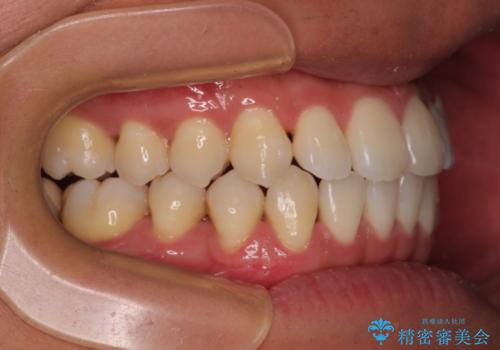

歯列弓の拡大により約1年で矯正治療を終えることができました。

正中も合わせることができ、非常にきれいに仕上がりました。